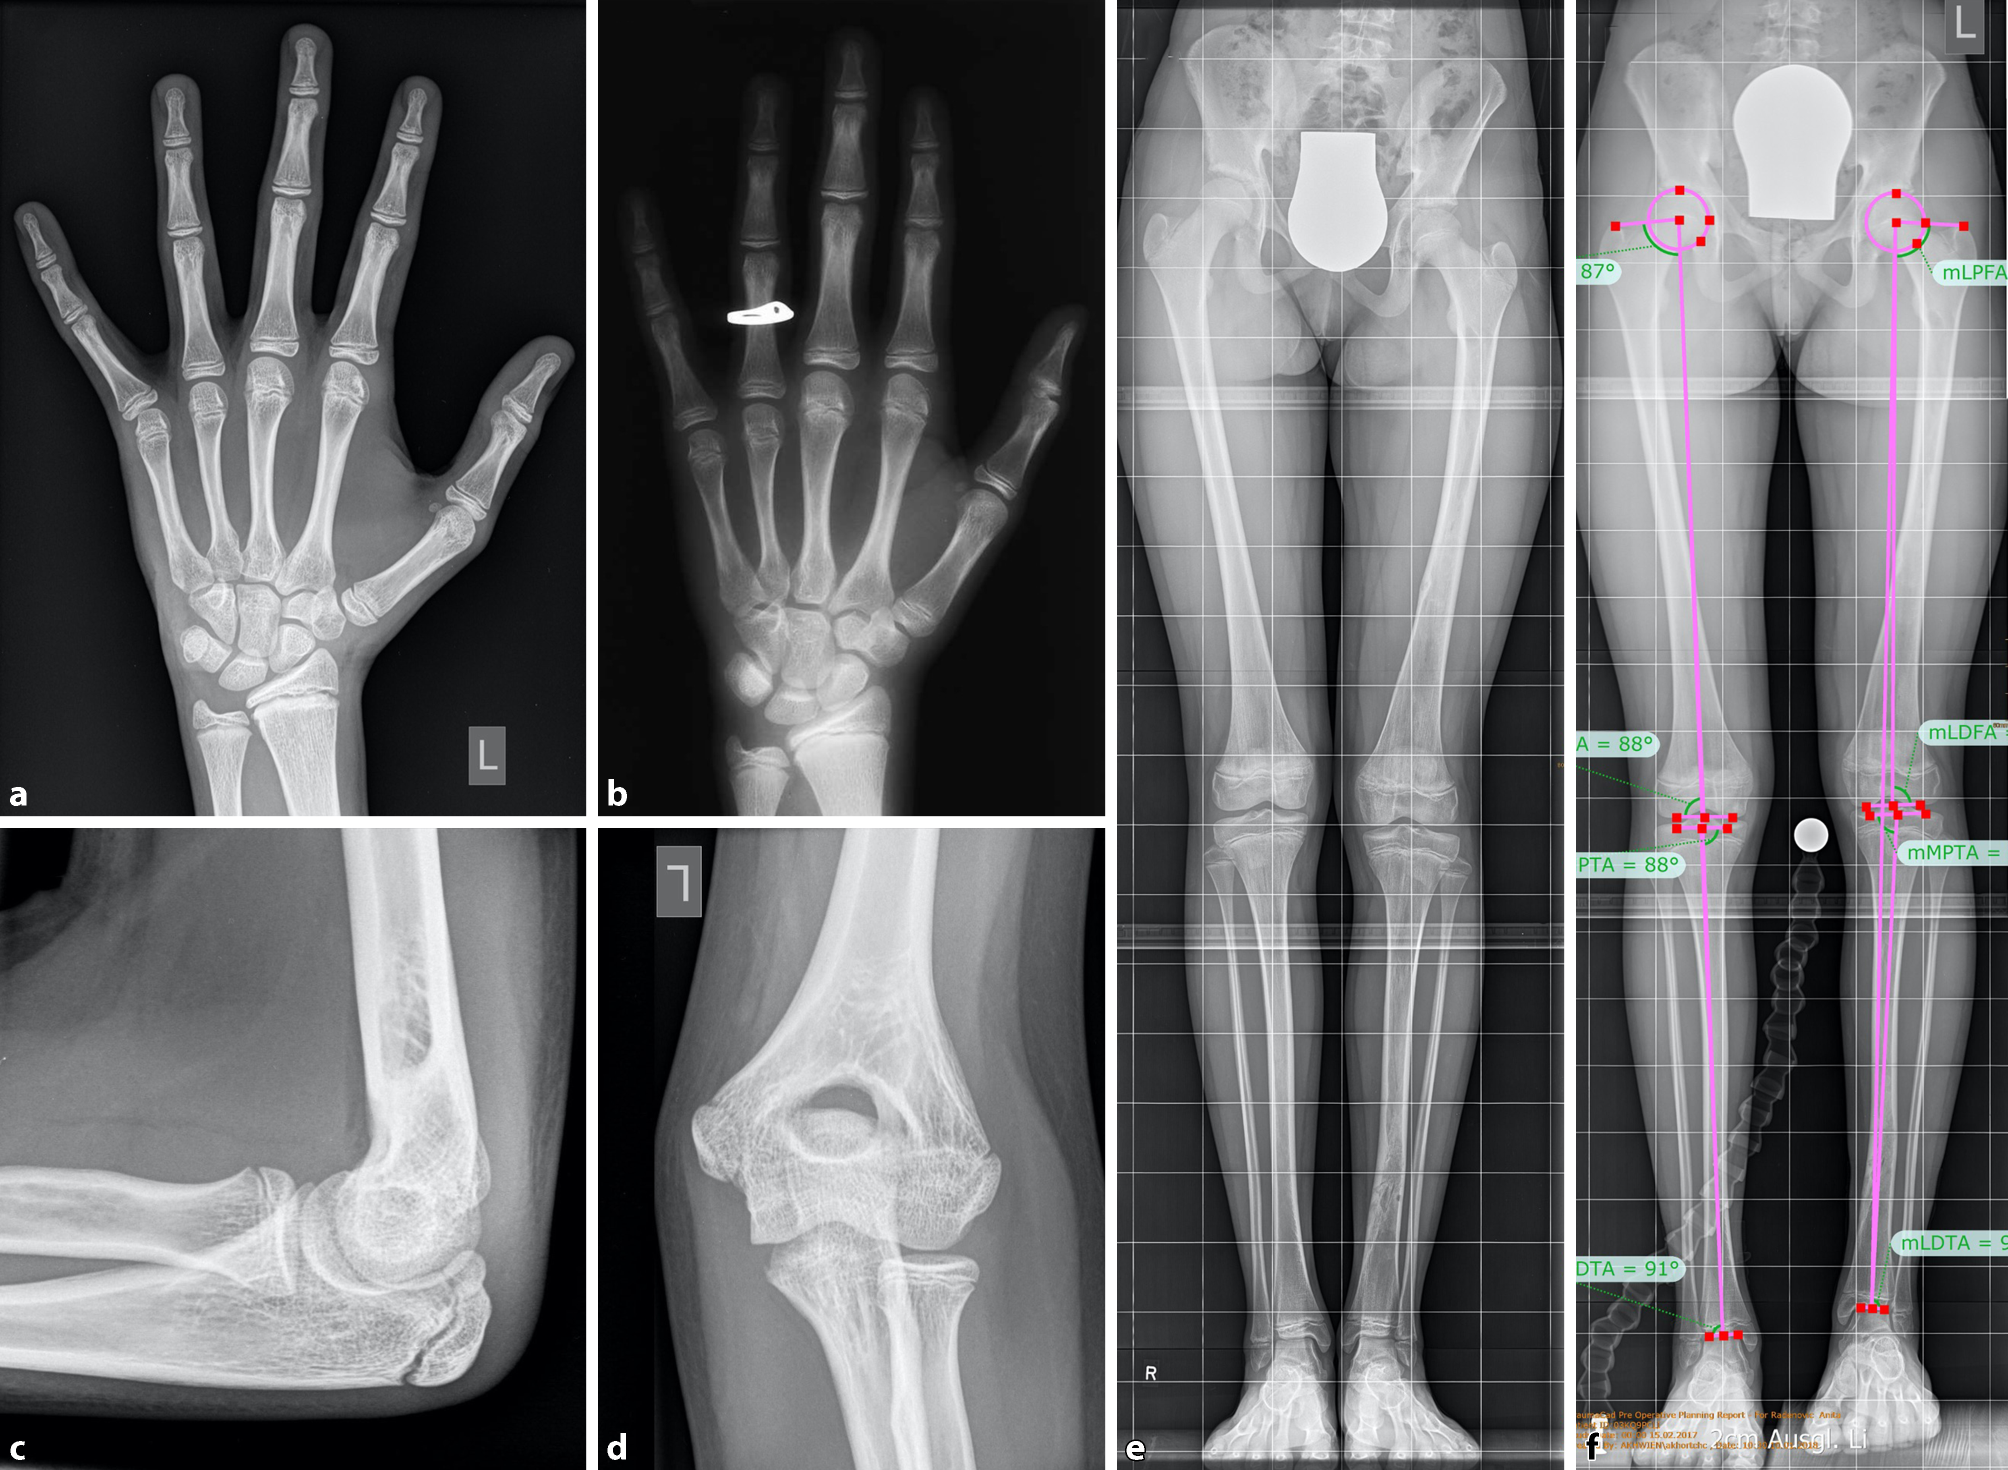

Chronological age is based on the actual years of age. Skeletal (bone) age is a maturity indicator which is based on a set of radiographic “norms” that allow us to make predictions about the future growth. The Greulich and Pyle atlas describes stages of ossification on a plain dorso/palmar (d/p) left hand x‑ray including the wrist ([18]; Fig. 2). Based on the Greulich and Pyle atlas, Bailey and Pinneau developed tables for prediction of adult height based on the bone age. Data of the Berkley Growth Study were used including 103 girls and 89 boys measured and x‑rayed from 8 years to 18 years of age once every six months (with occasional exceptions) [19].

Fig. 2

Example of bone age determination. A girl with chronological age of 12 years and 10 months. a Left hand X‑ray and b reference X‑ray according to the Greulich and Pyle atlas for a bone age of 11 years in girls. c Lateral and d antero/posterior (a/p) left elbow X‑ray to determine the bone age according to the Sauvegrain method. The evaluation results in 24.5 points corresponding to a bone age of 11.5 years in girls. The difference between the girls chronological age and the bone age is > 1 year speaking for a retarded bone age. e Full standing a/p bilateral lower extremity radiograph with a leg length discrepancy of −2 cm on the left side. f Preoperative X‑ray with 2 cm block under the left foot to equalize leg length discrepancy, and limb alignment measurements

The Tanner–Whitehouse and the short hand bone age method are other techniques for assessing the bone age in a left hand radiograph [20, 21]. The distinct features of ossification in the pediatric skeleton can be used to assign a bone age, and correlate the findings with the chronological age of the child. If the bone age appears younger than the actual age, a retarded bone growth can be detected. Vice versa, if the skeletal findings are assigned to an older bone age, accelerated bone growth is present. During the two years of pubertal growth spurt, the Sauvegrain method has been proven to be a reliable method. The Sauvegrain technique determines bone age from a/p and lateral left elbow radiographs using a 27-point scoring system (Fig. 2). The elbow is defined by distinct developmental series of its ossification centers, beginning at age 9 in girls and age 11 in boys. Fusion of the growth centers of the elbow is finished at the age of 13 in girls and 15 in boys [22]. The findings and differences between bone age and chronological age have to be taken into account for planning of surgical limb length corrections (i.e., epiphysiodesis). 50% of children have an accelerated or retarded skeletal age [14]. A bone age that deviates more than two standard deviations from the mean age is probably attributable to a pathologic state [17].